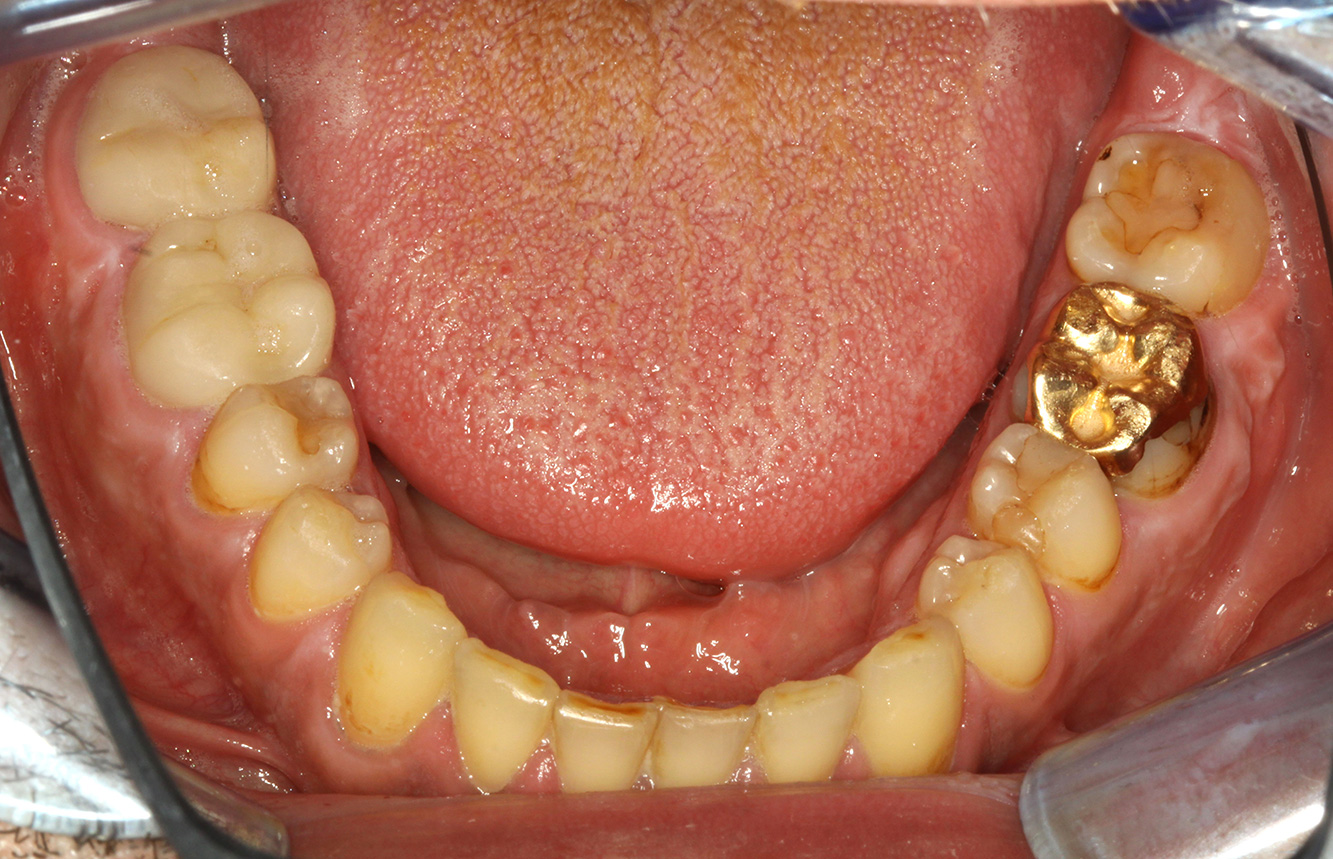

Der gesunde Patient mit parodontaler Vorerkrankung & Periimplantitis